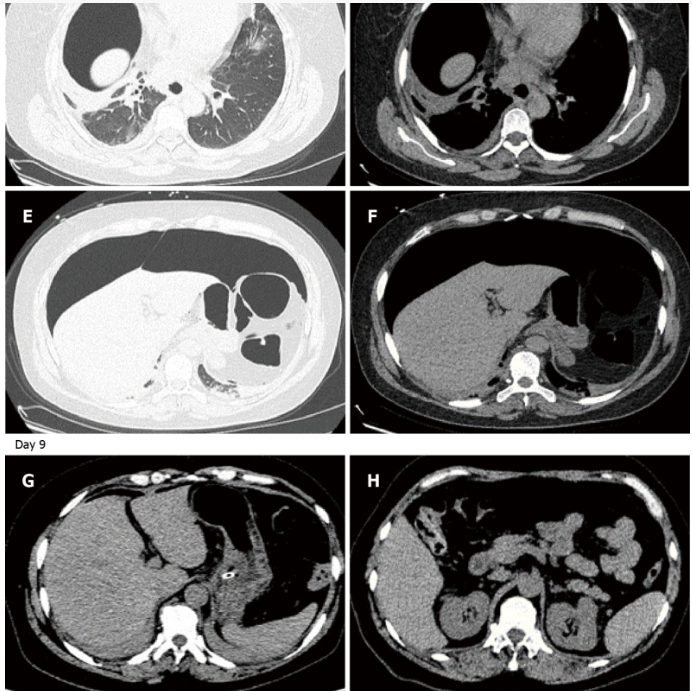

30分钟后,注射器内气泡量明显减少,患者诉腹部胀气显著缓解。行急诊胸腹部CT检查:纵隔少量积气,右侧胸腹壁及肌间隙多发积气,腹腔内仍残留大量游离气体,空肠少量积气伴管腔轻度扩张:下图A、B)。

后续治疗(其中留置胃管2天、禁食3天及支持治疗),复查腹部CT,显示气腹已基本消失(下图C、D)。经过两周抗生素治疗,肺部感染好转出院。